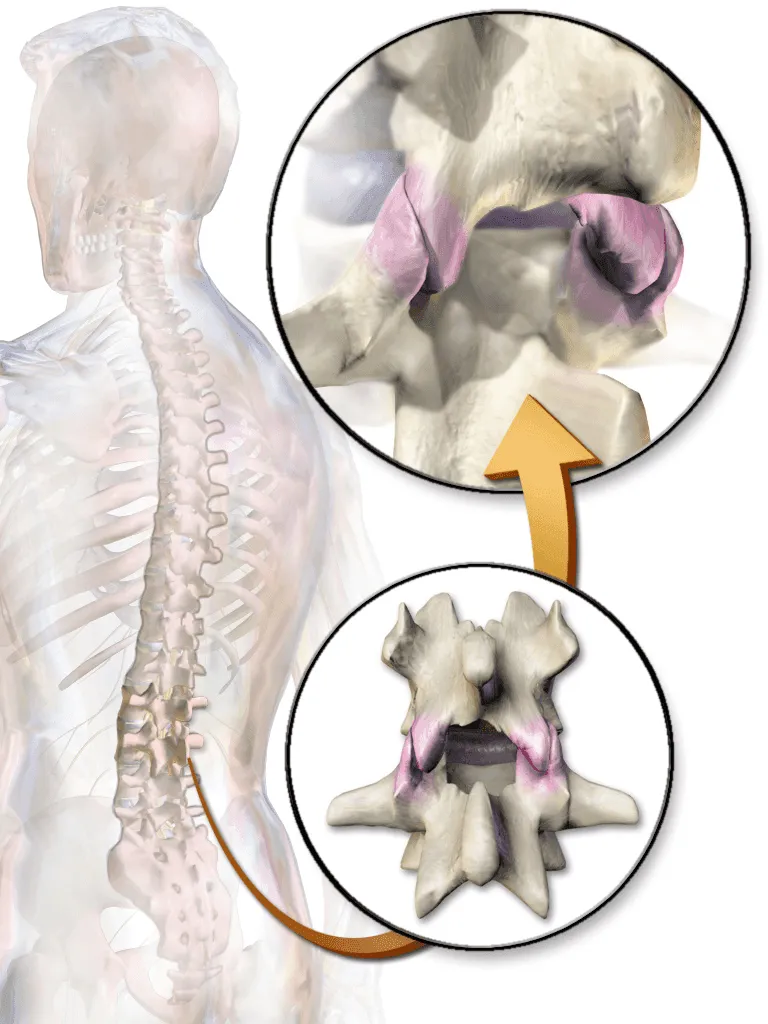

Illustration showing a transparent human figure with zoomed-in views of cervical facet joints.

Destroys Pedicle & Vertebral Body